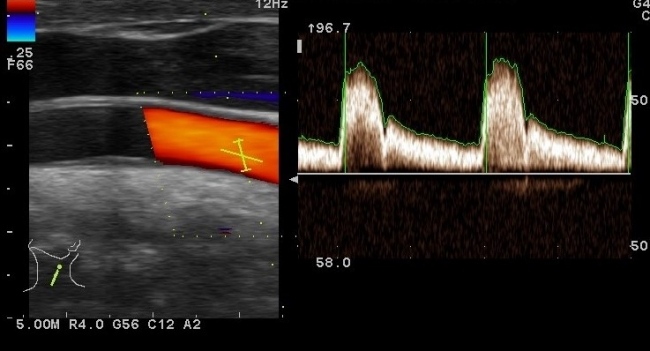

Ecografie Doppler Vasculară

Ecografia vasculară este dedicată studiului morfologic (structural) și hemodinamic (funcțional) al vaselor mari de sânge (artere și vene) dintr-o anumită regiune a organismului.

Ecografia vasculară cuprinde mai multe metode care sunt efectuate pe rând sau concomitent: ecografia bidimensională, Doppler și color. Procedura este neinvazivă, fiind necesară utilizarea unui gel special care se interpune între sonda de examinare și tegumentul pacientului. Poziția pacientului se alege în funcție de regiunea anatomică de examinat.